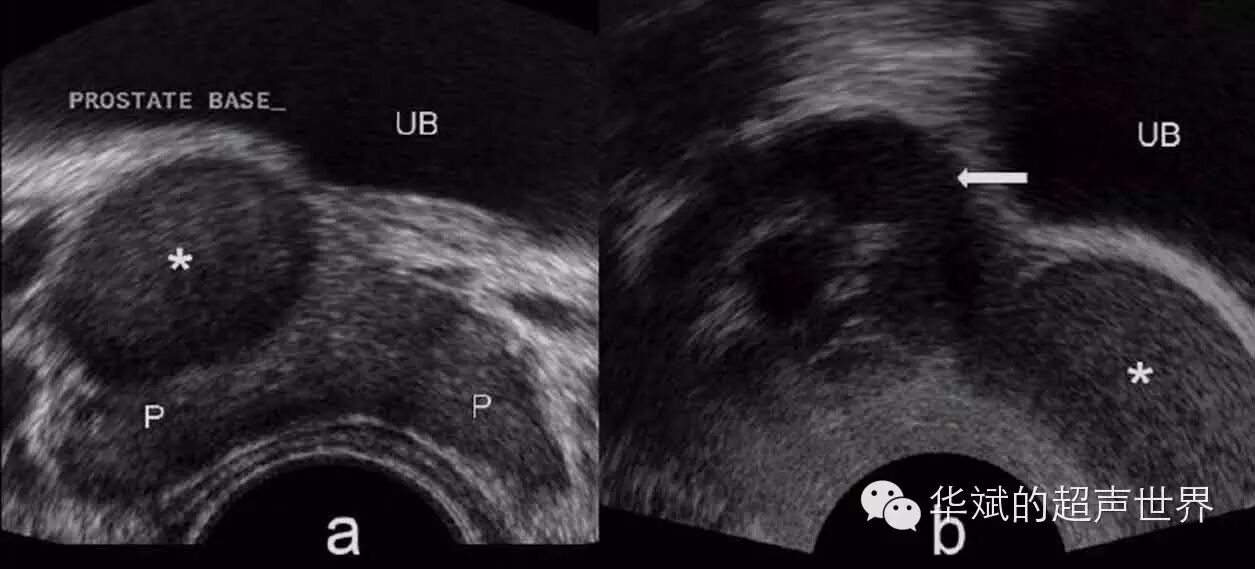

图4 精囊囊肿。右侧精囊区囊肿(星号)位于前列腺与膀胱之间。图a为经直肠横断,图b为精囊长轴扫查,箭头为扩张的精囊。P:前列腺,UB:膀胱。